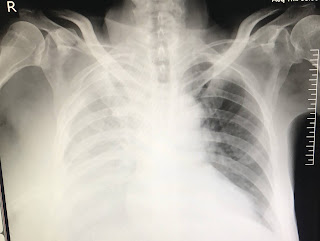

On x ray  there is presence of right sides pleural effusion which is almost the complete lung

Massive pleural effusion , icd placed